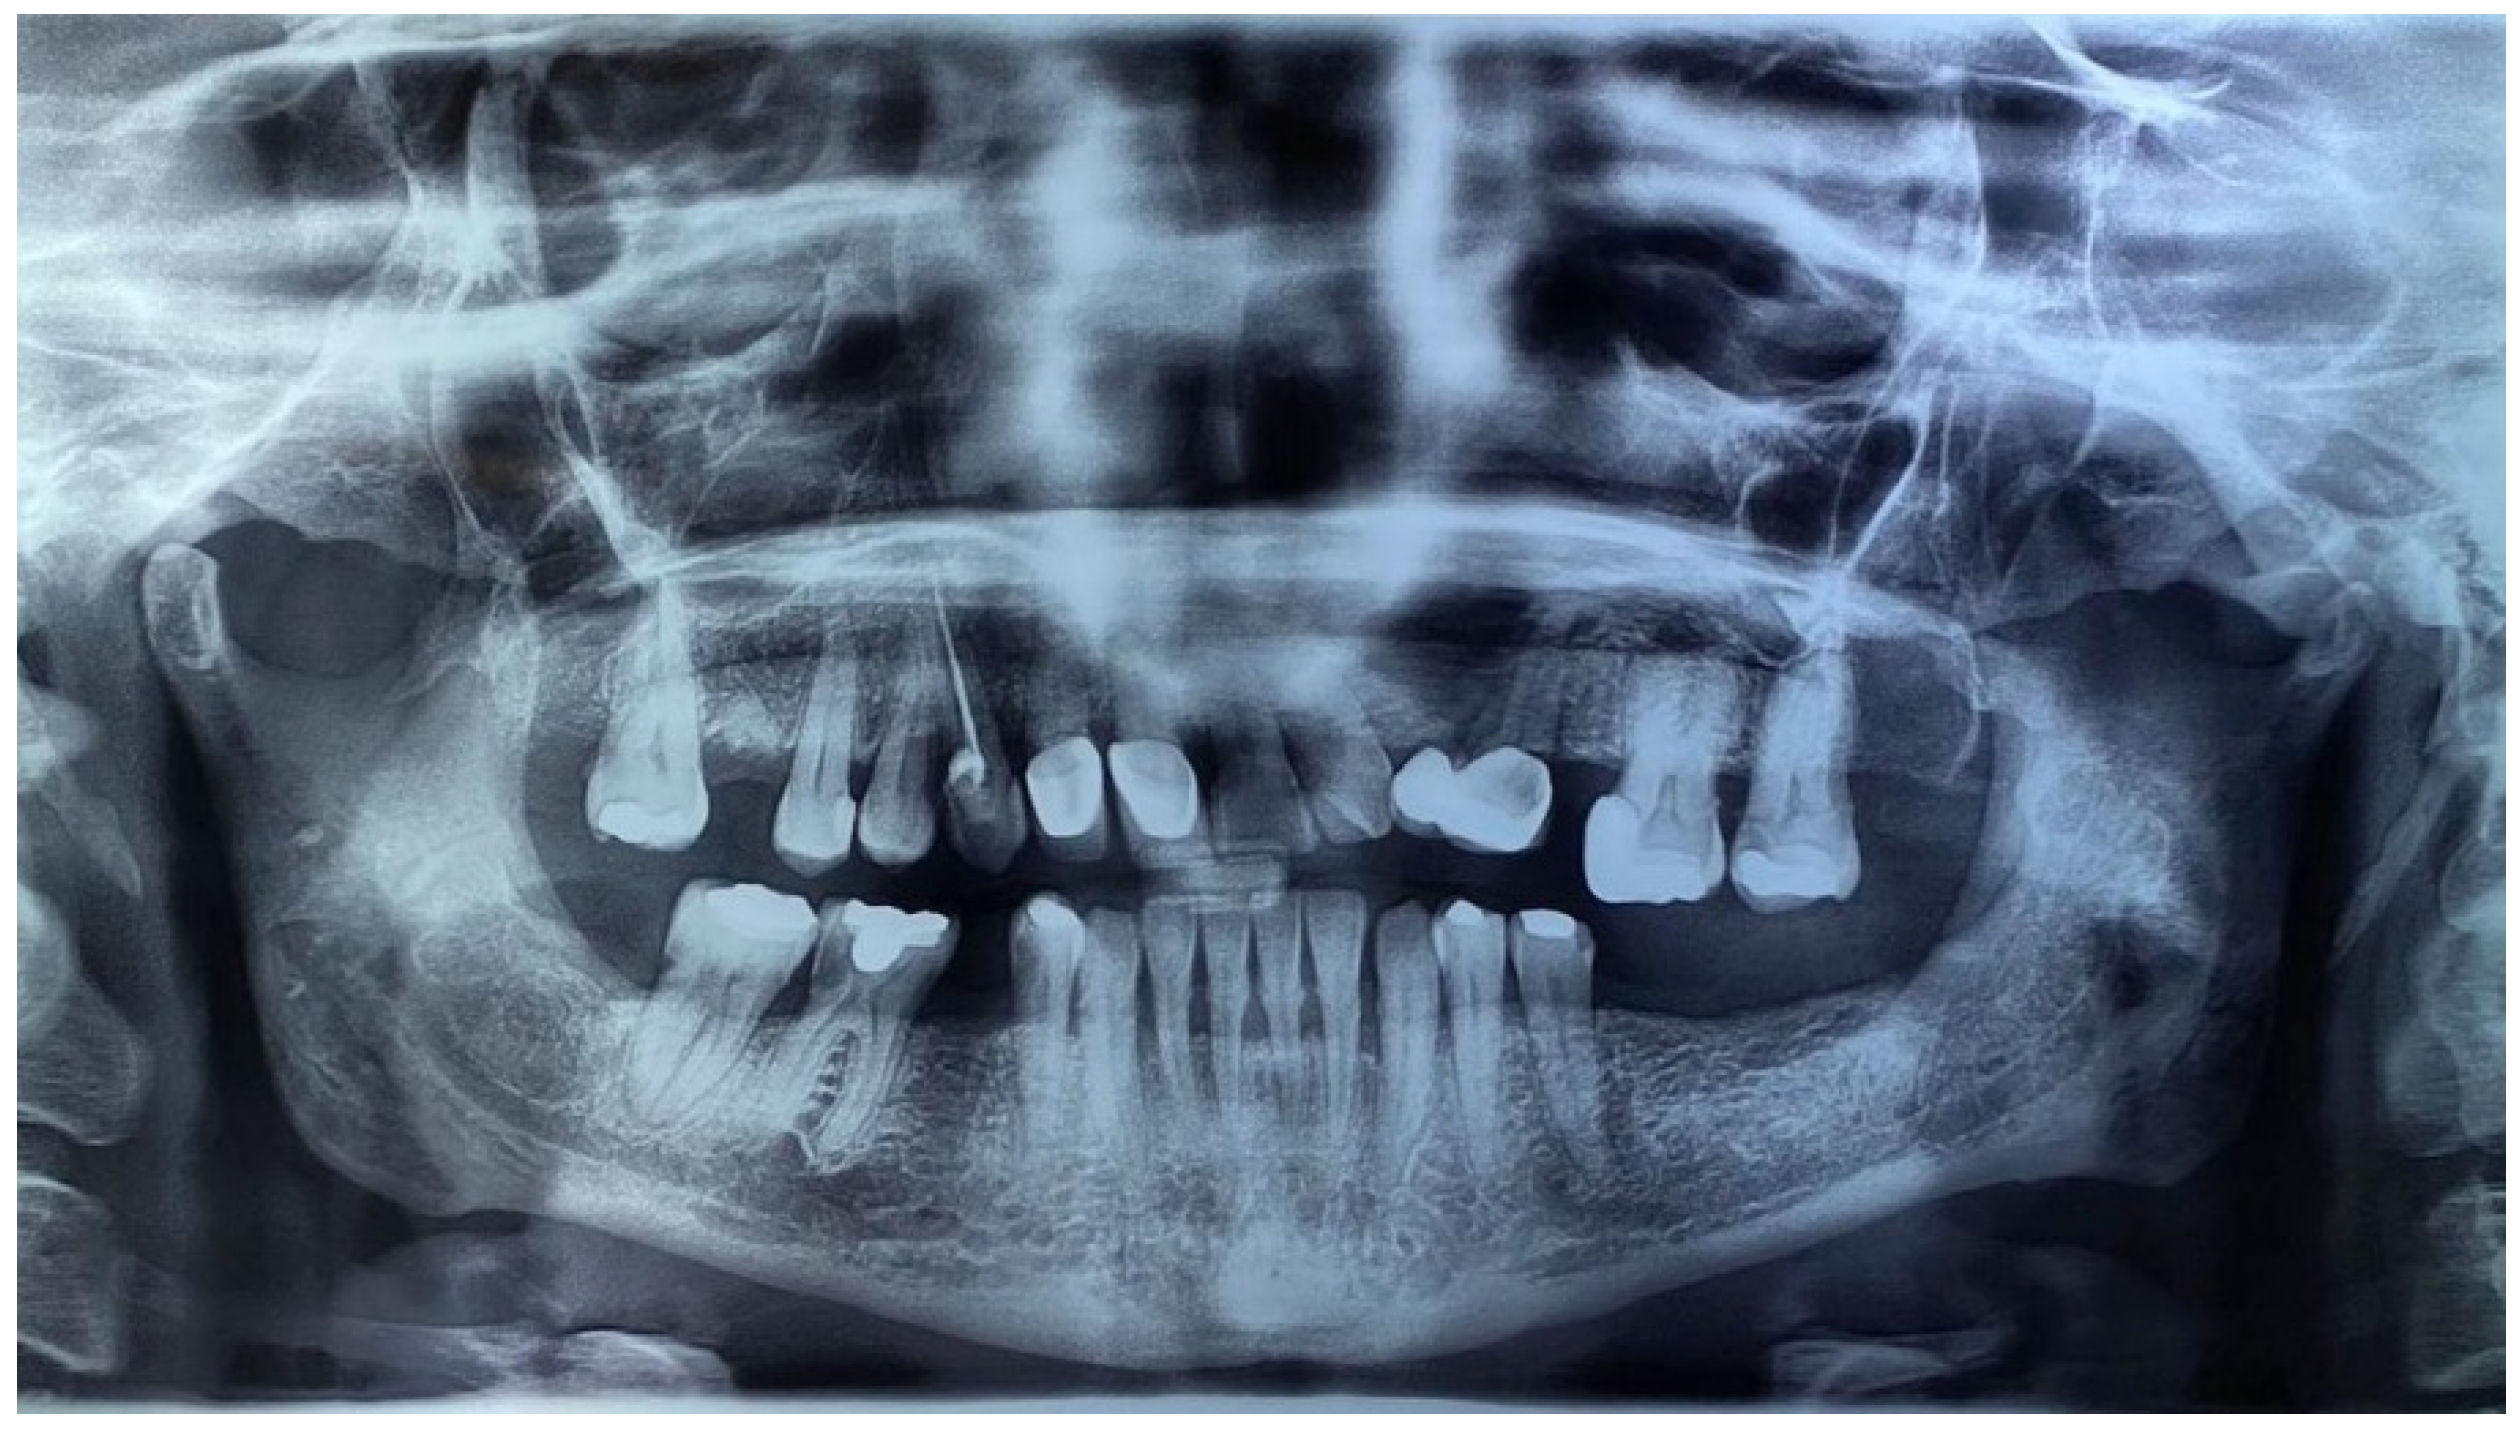

| Histologically confirmed odontogenic keratocysts | Congenital malformations: cleft lip or palate, bulging of the frontal bone, coarse facies, hypertelorism |